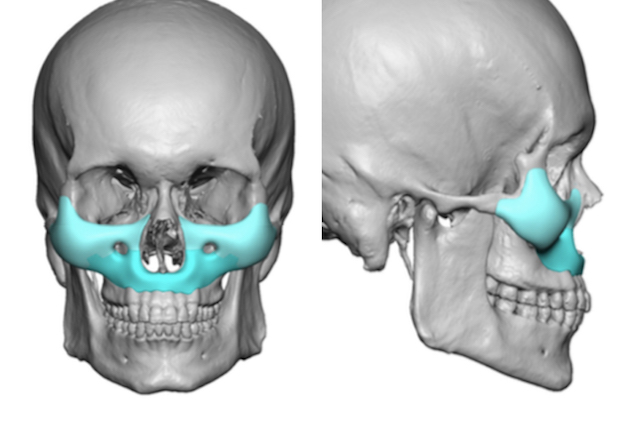

I know a guy who designed this for himself in collaboration with an asian implant company.

Not the final product yet, he is making adjustments as we speak.

Found a surgeon willing to insert it.

Giant and Eppley were the inspiration